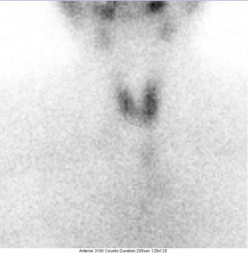

甲状腺显像正常图像: